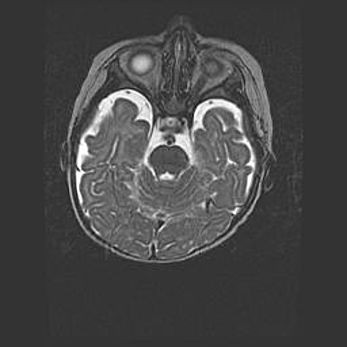

Подострая гематома правой гемисферы мозжечка.

Наружная гидроцефалия.

Возраст: 15 дней

Вес: 3100 г

Пол: женский

Окружность головы: 37 см

Срок гестации: 35-36 недель

При открытой наружной форме гидроцефалии у новорожденных расширяются и переполняются субарахноидные пространства.

Кровоизлияния в мозжечок имеют две клинико-анатомические формы: полушарные гематомы и кровоизлияния в червь.

К появлению этой патологии может привести: повреждения головного мозга, возникающие в результате асфиксии и гипоксии плода при беременности, или травмы во время родов. Редко гематома мозжечка может быть результатом первичной коагулопатии и сосудистой мальформации, диссеминированном внутрисосудистом свертывании, изоиммунной тромбоцитопении.